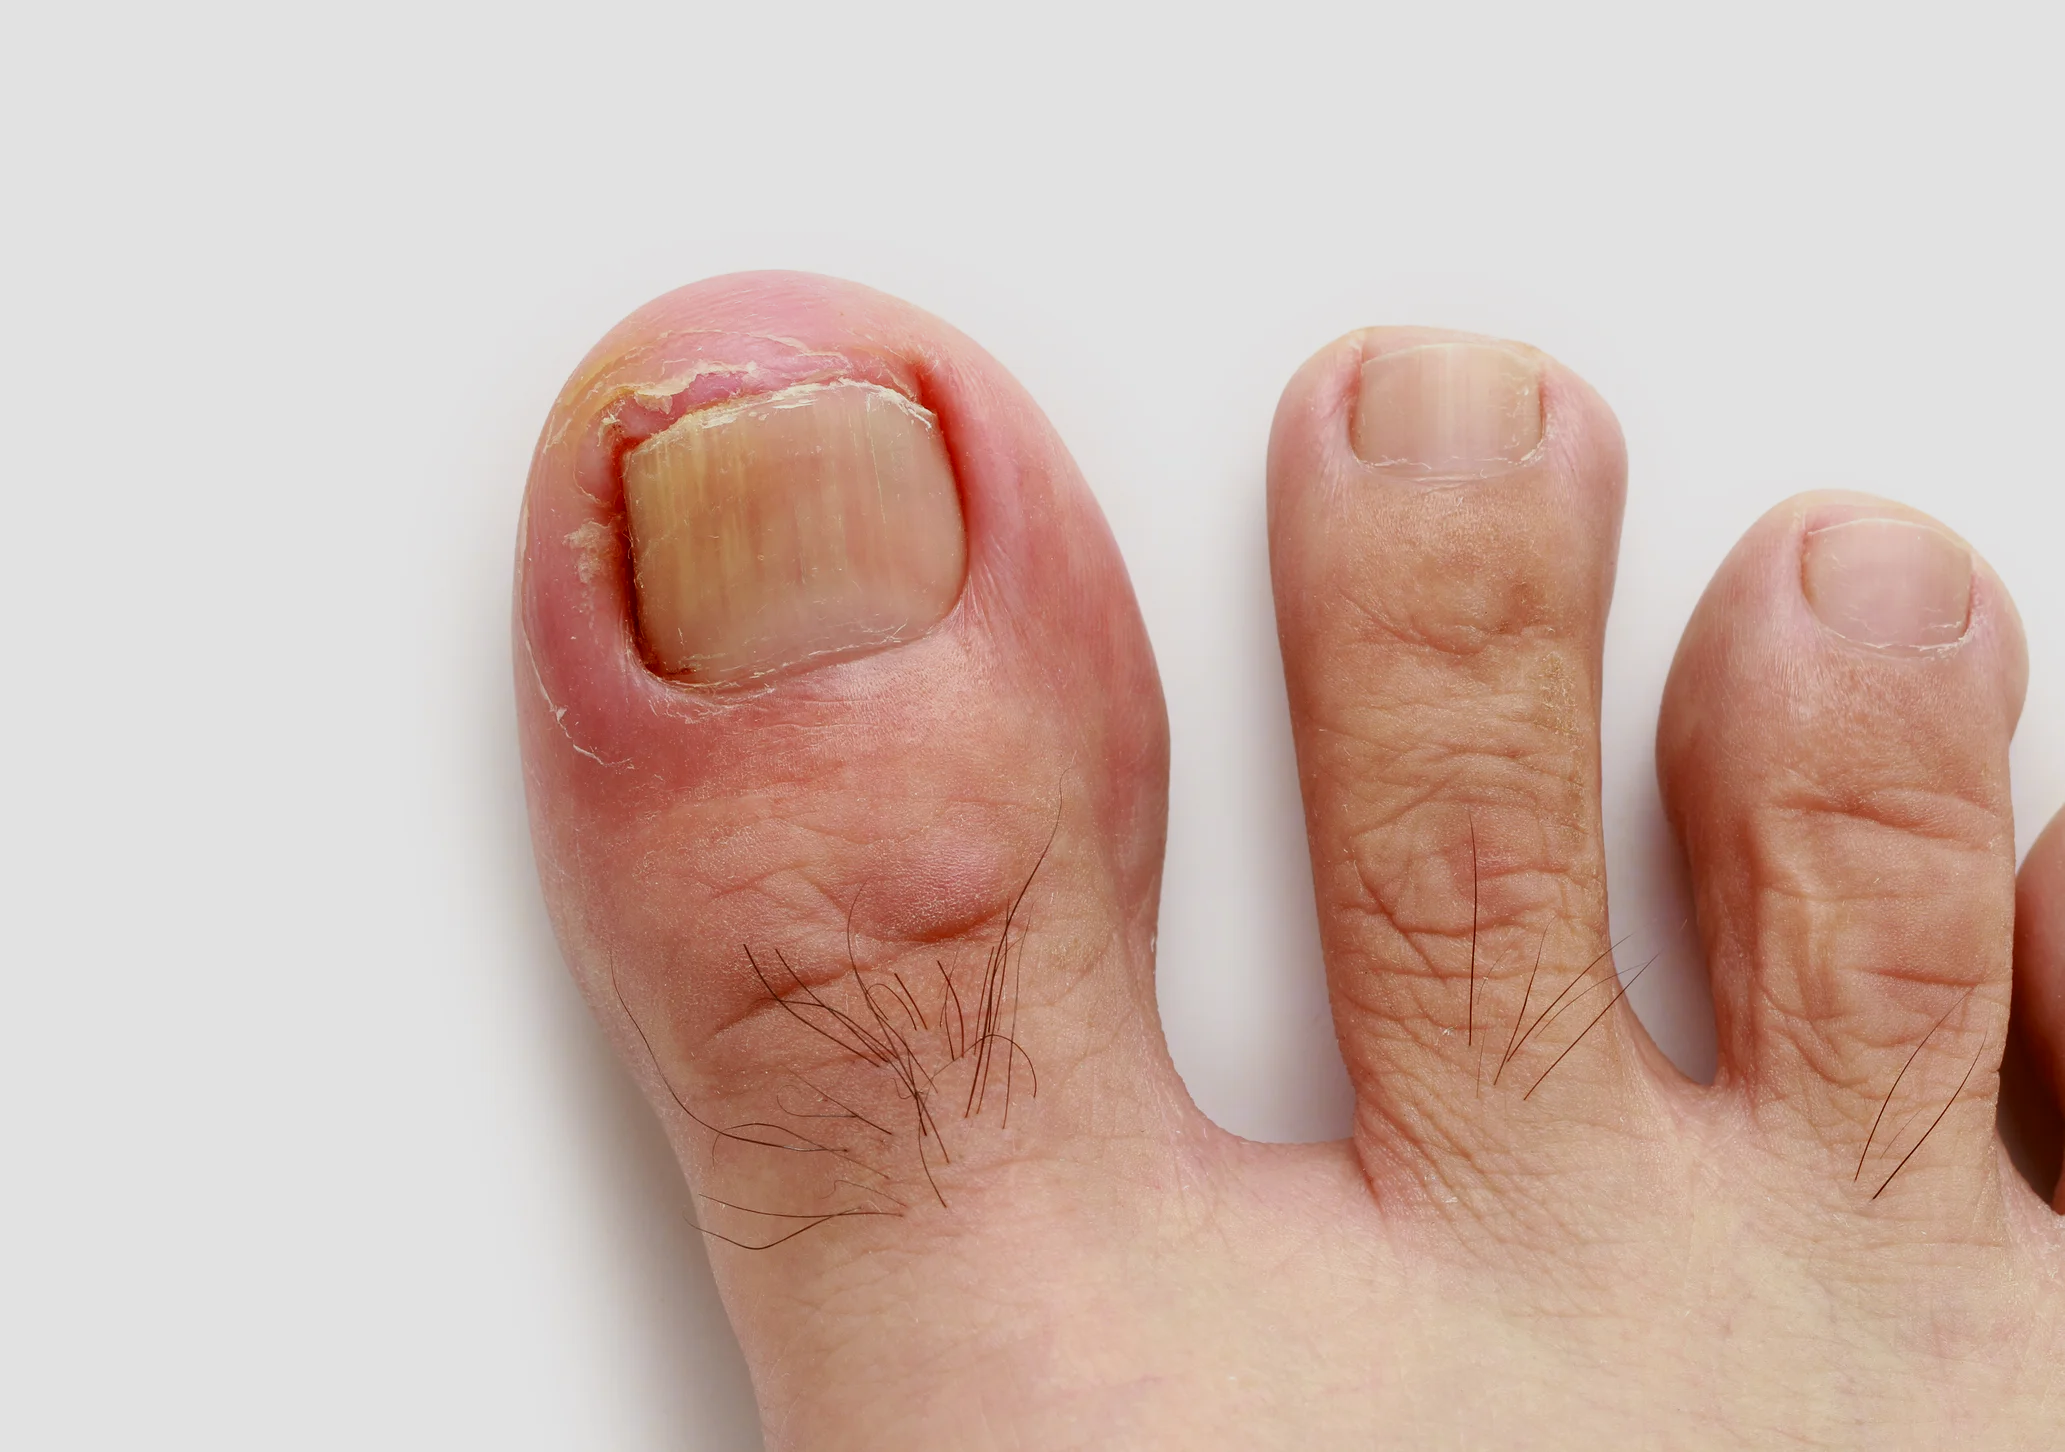

Ingrown Toenails

Ingrown nails are indeed just that! The nail edge has cut or buried itself into the flesh around the nail edge. Read more >>